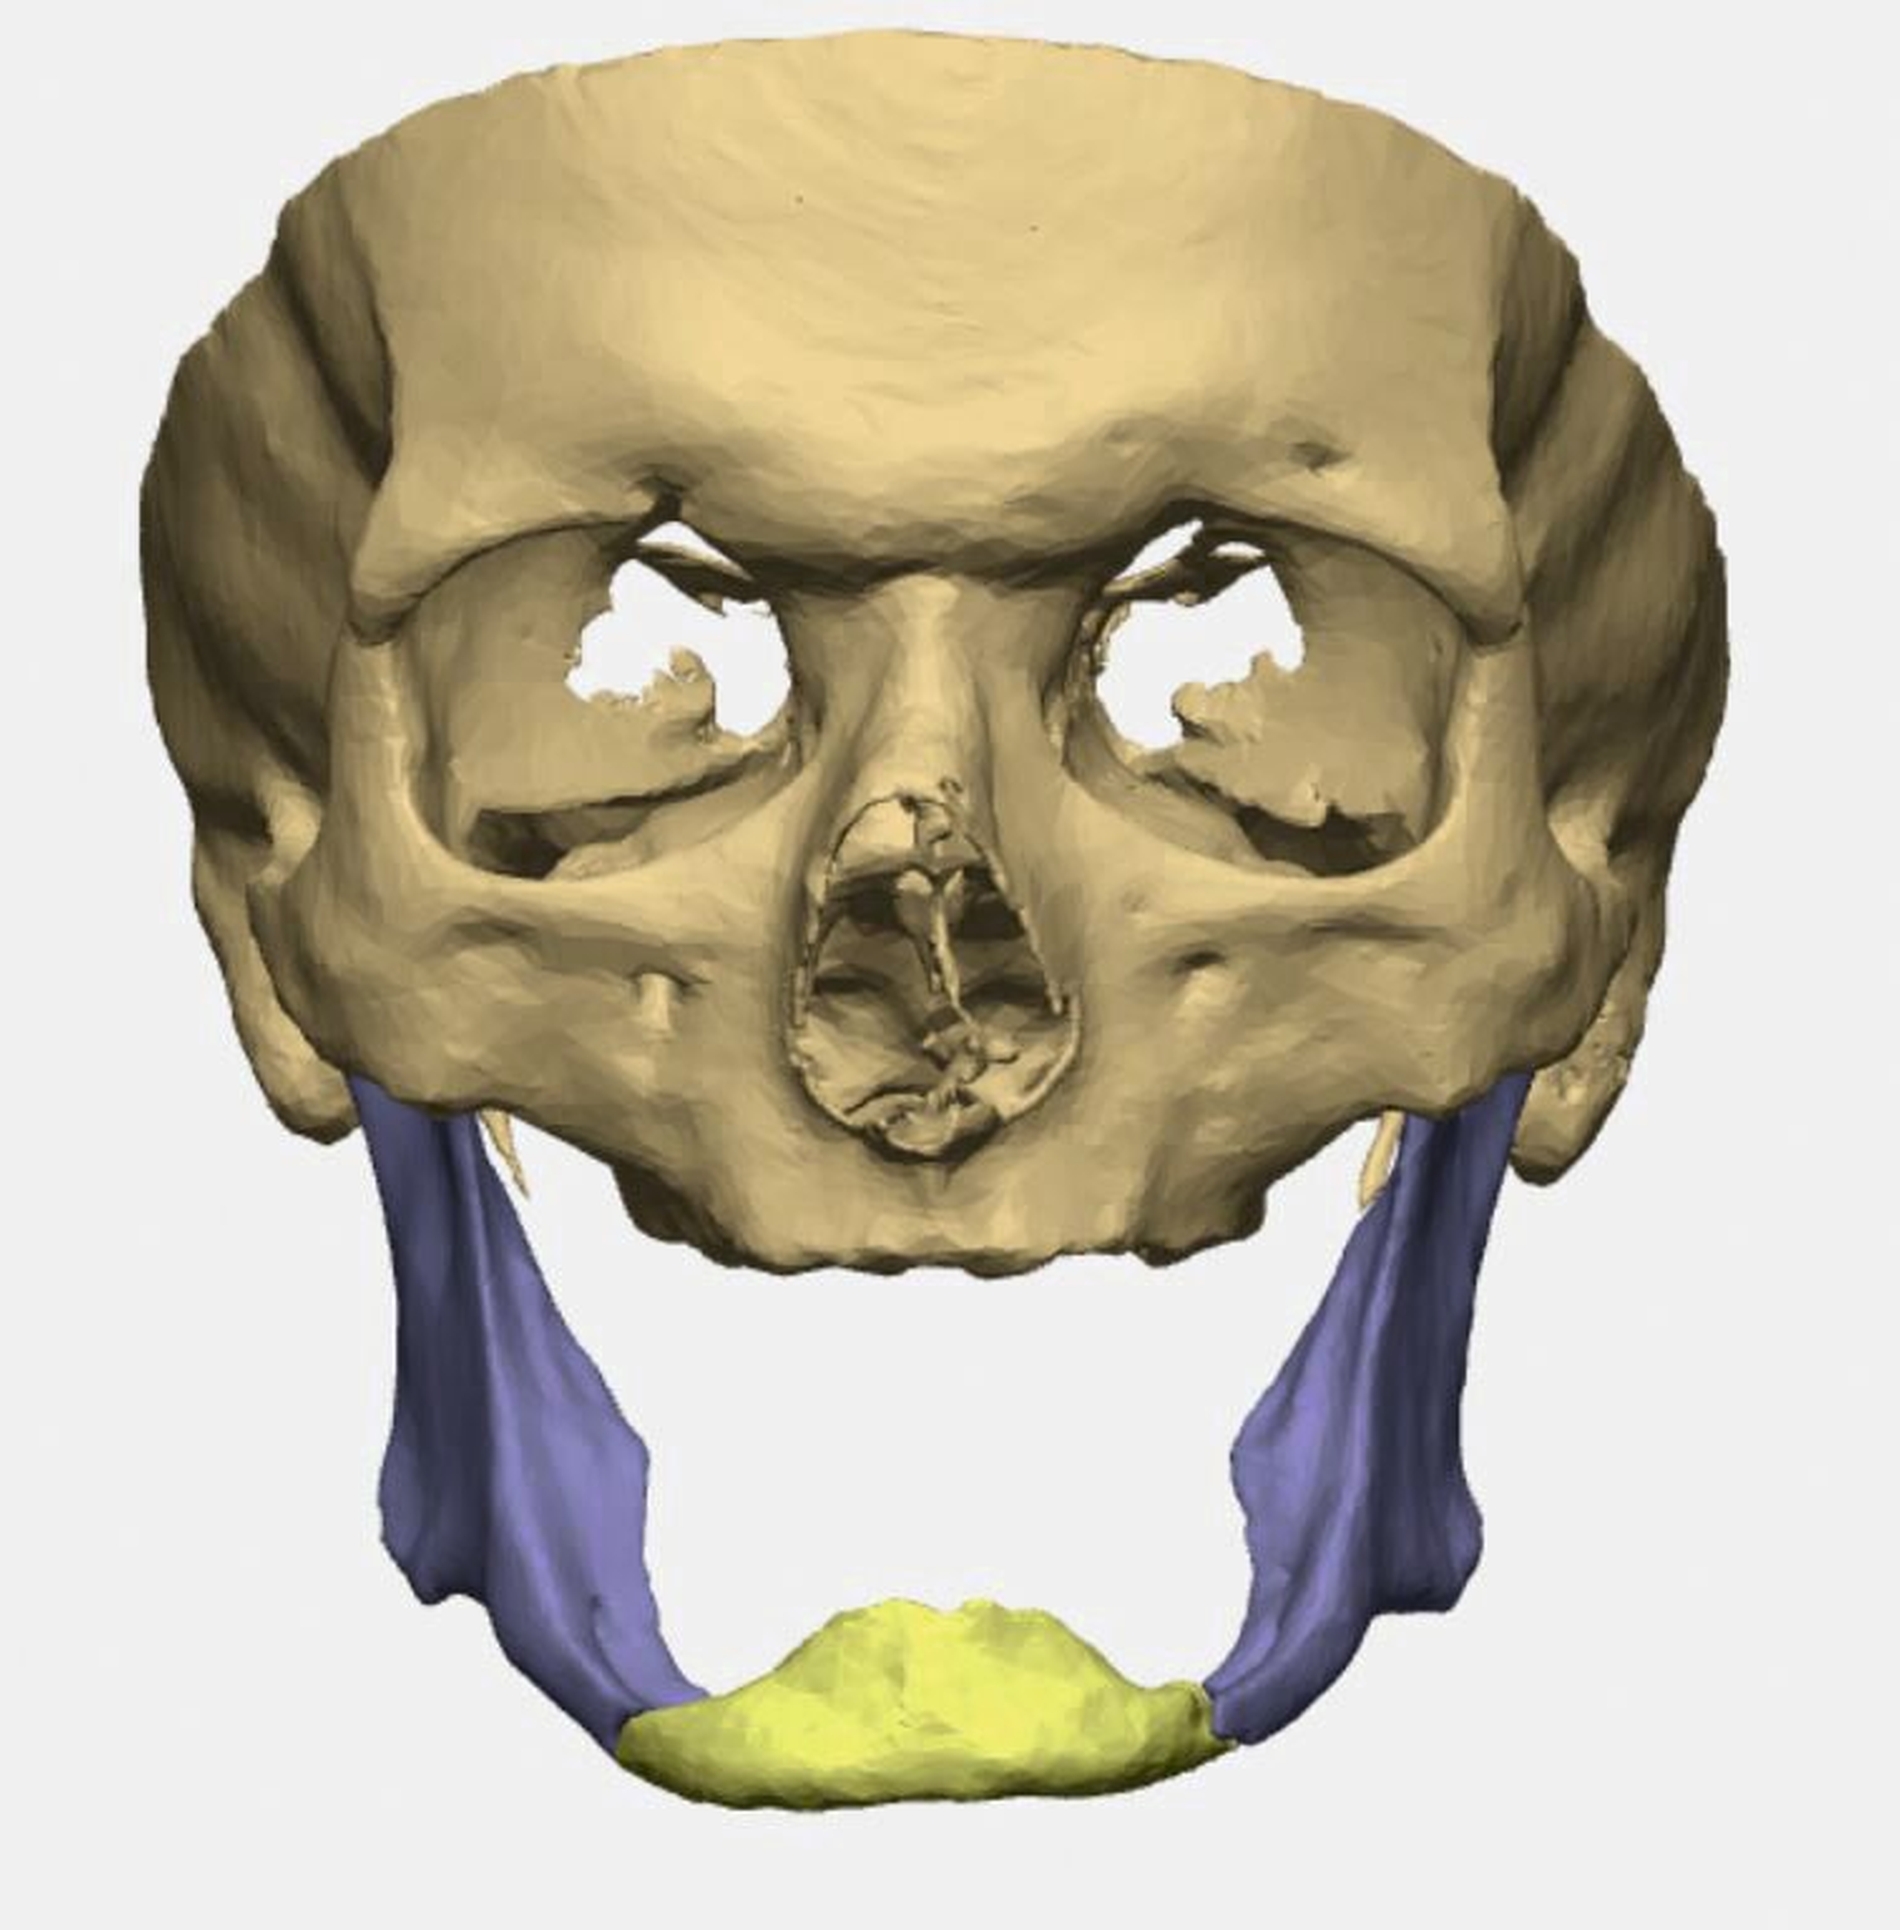

Bei zahnlosem Ober- und Unterkiefer erfolgte die virtuelle Repositionierung des frakturierten Unterkiefers (Abbildung 2a). Mittels CAD/CAM-Verfahren wurde eine stabile Rekonstruktionsplatte aus Titan (patientenspezifisches Implantat; PSI) geplant und hergestellt. Dabei sollte die Position des PSIs im Bereich des Unterkieferkorpus weit kaudal an der Basis sein, so dass später bei der Anpassung einer neuen Unterkieferprothese keine Interferenzen auftreten (Abbildung 2b).

Gleichzeitig konnte durch eine optimierte Bohrlochposition der Nervus alveolaris inferior geschont werden, eine Neurolyse brauchte nicht geplant zu werden. Außerdem wurden an die Zielreposition angepasste Bohrschablonen (drilling guides) hergestellt, die ein Vorbohren der späteren Schraubenlöcher in der exakten Zielposition ermöglichen (Abbildung 2c). In Kombination mit dem PSI sollte so eine Auto-Reposition des Unterkiefers durch die vorgegebenen Bohrlöcher erfolgen.

Durch einen frühzeitigen Zahnverlust im jungen Erwachsenenalter – zum Beispiel durch Trauma oder kariöse Zerstörung – kann es im Laufe des Lebens aufgrund der fehlenden Belastung durch das Kauen zu einer ausgeprägten Atrophie des Unterkiefers kommen. Dieser sogenannte Pencil Bone oder auch Bleistiftknochen neigt insbesondere bei gleichzeitig bestehender Osteopenie/Osteoporose zu einer Frakturierung bei schon geringen Traumaeinwirkungen. Dabei treten meist ein- oder beidseitige Unterkieferkorpusfrakturen auf. Bei beidseitigen Frakturen kann das mediane Bruchstück aufgrund des Zuges der Zungengrundmuskulatur nach kaudodorsal abgedrängt werden [Madsen et al., 2009].